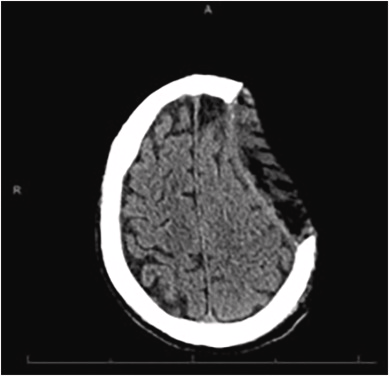

Happy Sunday! Check out this fascinating case about an internal carotid artery pseudoaneurysm presenting as a peritonsillar abscess in a 14-year old with persistent sore throat and emesis after dental work. sciencedirect.com/science/articl…

"The patient's original pharyngitis was thought to have developed into a cellulitis, creating a phlegmon that rapidly compromised and eroded into the carotid sheath, leading to separation of the internal carotid artery walls and the development of the pseudoaneurysm."

"Cases like this illustrate the need to keep internal carotid artery pseudoaneurysms in the differential, especially given children's susceptibility to infectious arteritis "